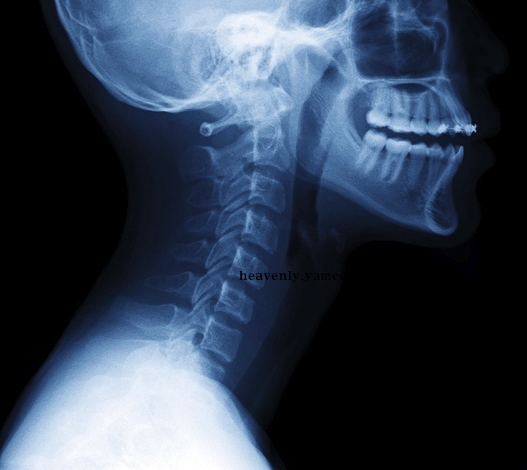

목디스크는 경추 즉 목뼈 사이의 디스크가 빠져나오거나 뼈조직이 목으로 지나가는 척추 신경을 압박하여 통증을 발생시키는 것입니다. 발생 원인으로 알아보면 평소 바르지 못한 자세, 접촉사고, 충격여파 등 다양한 요인들이 있습니다.

가는세월 절대로 막지 못합니다. 세월이 흘러 나이를 먹으면 자연적으로 발생하는 것이 목디스크 증상 이기도 합니다. 그 이유는 인간의 추간판이 탄력성을 잃게되어 섬유륜에 균열이 생긴다고 합니다. 따지고 보면 나이를 먹으면 먹을수록 자연스럽게 발생하는 것이라고 생각하면 되겠습니다.

이는 디스크 수핵이 탈출하여 척수가 눌리게 되면 팔의 힘이 약화 되는데 축수가 압박된 정도에 따라서 한 쪽 팔의 마비 또는 저림 증상이 나타나며 손가락 감각 이상 증세를 보이기 때문입니다.